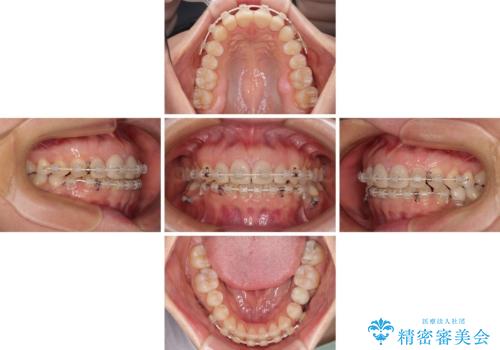

- 大きすぎる上顎前歯と、隙間の空いた下顎歯列を気にして来院された患者様です。

上顎前歯にはセラミッククラウンが装着されており、顔や他の歯と比較して幅の大きい状態でした。

下顎前歯は空隙歯列弓であったので、アンカースクリューとワイヤー装置を用いてスペースを閉じていくこととし、上顎前歯は矯正治療用の仮歯に置き換えた上で、仮歯の大きさを削って小さくしながら、上下前歯部の部分矯正を行うこととしました。

矯正治療後は、仮歯とした上顎前歯をオールセラミッククラウンにて補綴治療を行うこととしました。

日本と海外を拠点に仕事をされていらっしゃるため、数ヶ月治療があいてしまうことがあり、期間はかかりましたが、2年間で望み通りの前歯に仕上げることができました。